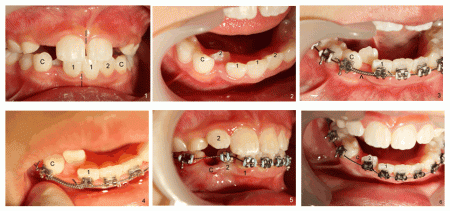

Alice七歲時,下頜側切牙錯位(圖二:2),不利於局部清潔,而且下頜中線偏移(圖一:虛線),需要早期矯正。

四個月後,下牙相當整齊了(圖三),在中切牙(1)與乳尖牙(C)之間放置一個彈簧(箭頭),為錯位的側切牙創造空間。一個月後,空間有所增加(圖四),但是之後進展緩慢,最後發現乳尖牙鬆動,不得不拔除(圖五),這樣側切牙就有足夠空間移動,三個星期,初見成效(圖六)。不久側切牙就位,最後為尖牙創造空間,去除矯正器,下前牙整齊(圖七),上下中線在一條線上(虛線),為了鞏固勝利成果,安裝固定維持器(圖七、圖八),其中一部分固定尖牙空間(圖八箭頭)。五個月後,維持器鬆動,本來應該重新固定,但是Alice母親不同意,不過牙齒還沒有移位,中線仍正常(圖九虛線)。